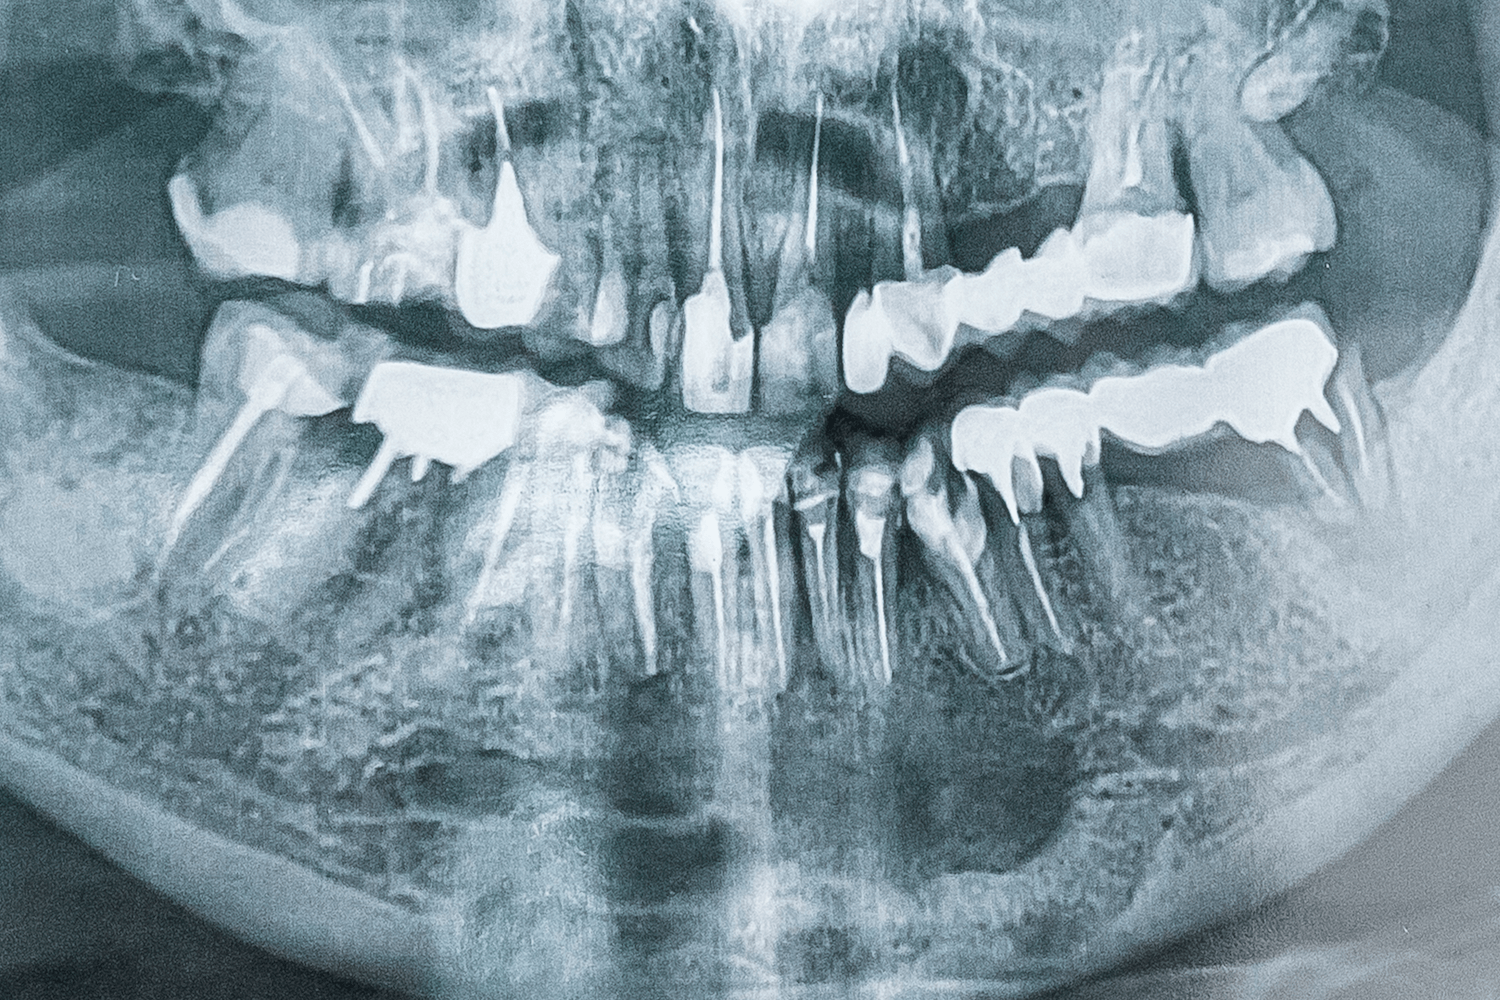

Около десяти лет назад к нашему врачу Максиму Макаренко обратилась пациентка с целью получить альтернативное мнение врача. Во время диагностики на панорамном снимке врач обнаружил интактные (здоровые) зубы на нижней челюсти и в области подбородка, в области апексов фронтальных зубов кисту с четким очертанием. Киста была достаточно большого размера, а именно от зуба 4.5 до зуба 3.5. То есть почти все зубы нижней челюсти были поражены новообразованием.

Дополнительно пациентку беспокоило онемение губы с обеих сторон, низа подбородка (из-за давления кисты на выход нерва из ментального отверстия).

После осмотра, изучения ОПТГ-снимка и выслушав жалобы пациентки, врач обнаружил зуб, вызвавший образование кисты (зуб 3.2) и предложил лечение, которое позволит сохранить все зубы. Пациентка согласилась на лечение, состоявшее из следующих этапов: